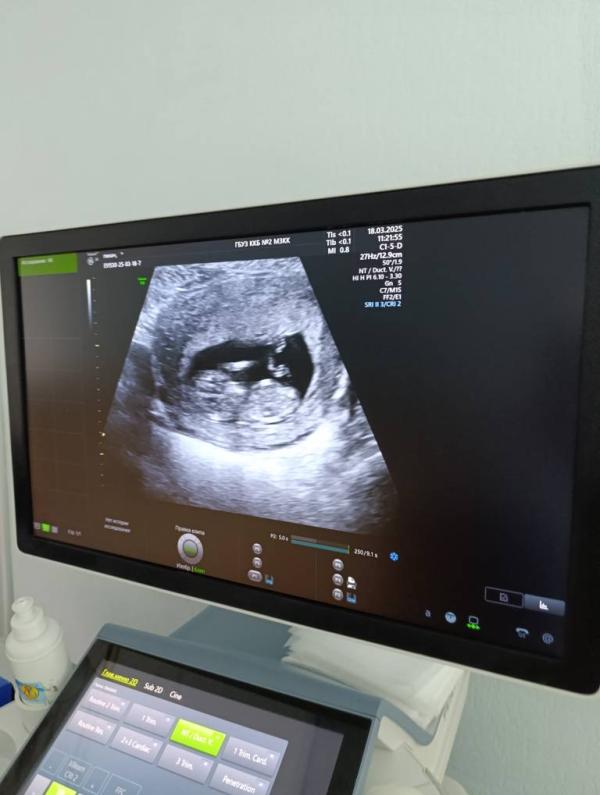

Я быстро сфотографировала монитор , там как раз осталось фото . (1фотка ).

Приехала в клинику , только зашла в кабинет , Элеонора Александровна успокаивает , говорит не переживай все посмотрим . Смотрит вагинально и по животу . развернула мне монитор, ребёнок активный , носик в порядке , твп 1.1 , говорит , странно , вполне можно было сделать скрининг , все абсолютно в порядке , ктр 53 , все соответствует сроку .